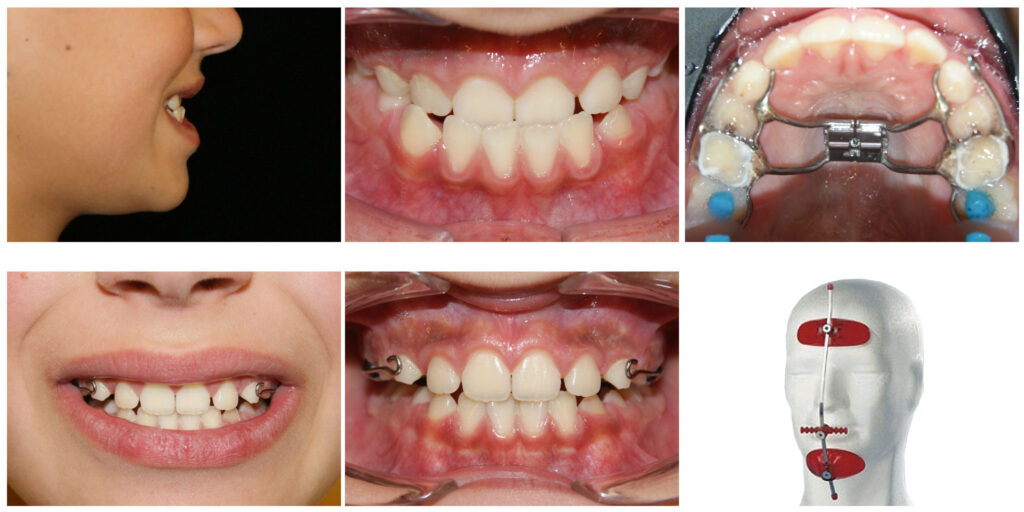

Corectarea muscaturii inverse cu forte extraorale – masca Delaire și disjunctor maxilar. Câteva luni pentru rezultate de care copilul se bucură întreaga viată

Corectarea muscaturii inverse cu forte extraorale – masca Delaire și disjunctor maxilar Alegem aparatul potrivit la vârsta potrivită